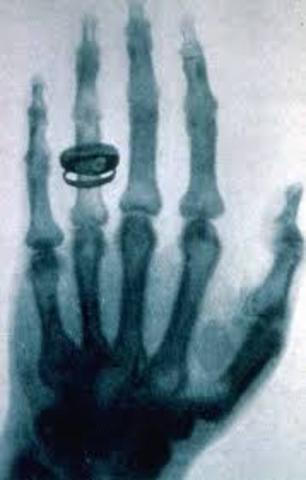

• Wilhelm Roentgen deicovered x-rays

Wilhelm Roentgen deicovered x-rays

this allowed doctors to see inside the body